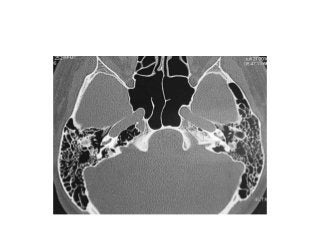

Temporal bone CT. Look at the sub-cochlear canaliculus or sub-cochlear

tunnel that can allow endoscopic transcanal retrocochlear access to the IAC

and drain the petrous apex cells